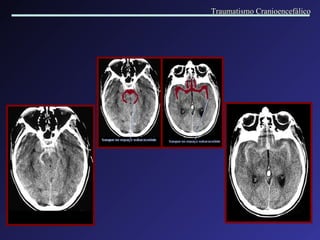

Golpe e Contra-Golpe Trauma que ocorre em dois locais do encéfalo quando a cabeça do paciente é bruscamente acelerada. O “golpe” ocorre no local do encéfalo que sofreu o impacto direto, o “contra-golpe” ocorre no lado oposto devido a um  deslocamento contralateral do cérebro. Traumatismo Cranioencefálico

A lesão por golpe e contra-golpe ocorre devido a dois mecanismos de injúria: a contusão, e a “cavitação”. Traumatismo Cranioencefálico

Traumatismo Cranioencefálico